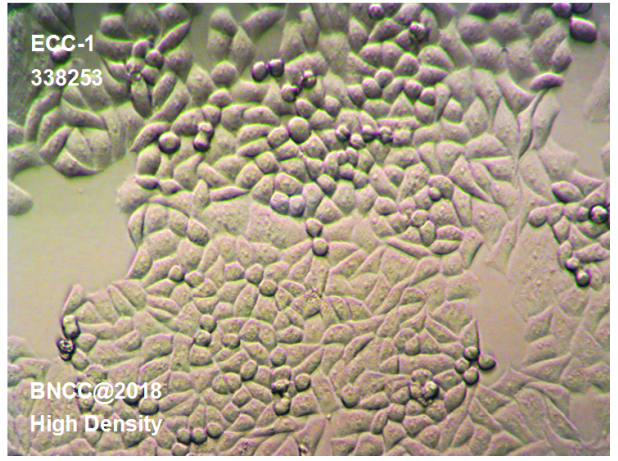

| 资源名称 | 子宫内膜癌细胞株 |

| 种属 | ECC-1 |

| 形态 | CM2-1培养液中,贴壁,上皮细胞样,多角形,紧密排列 |

CM2-1培养液中,贴壁,上皮细胞样,多角形,紧密排列